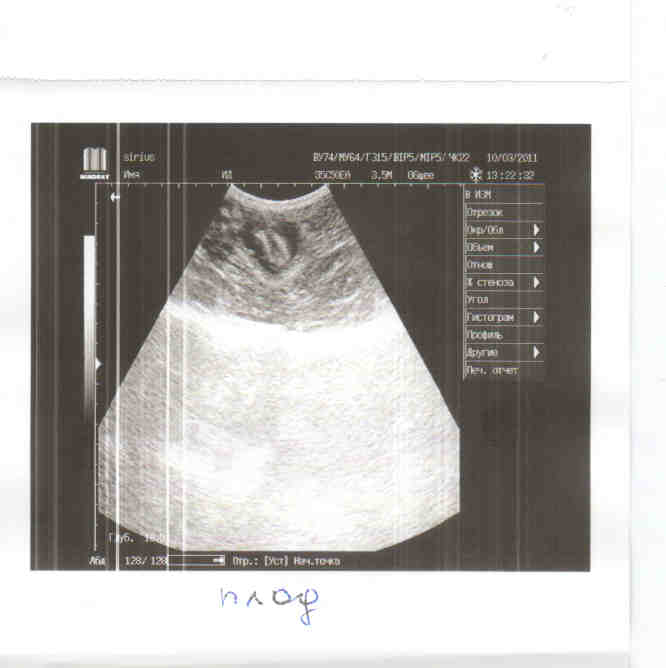

Сегодня, когда пришла за кошкой, обнаружили у нее сильный кровоподтек и запекшуюся кровь на животике. Повезла в Сириус (т.к. есть УЗИ, стационар), когда брили пузико, обнаружилась большая гематома и дырочка с кровью, толи кто- то ударил, может собака или напоролась на что то. Все конечно обработали. На УЗИ показало, что кошка беременна, на большом сроке 40-45 дней.

Мне нужна финансовая помощь, конечно большая часть с меня, но все я не потяну сразу. Выкладываю лист назначений, еще не посчитан стационар, т.к. неизвестно как пройдет операция. По состоянию кошка в норме, температура нормальная, почки в норме, а вот с печень небольшие проблемы, нужно будет ее поддержать.